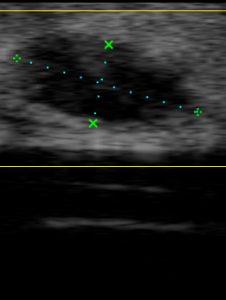

🔹 Caso 2: “Un bulto en la ingle que aparece solo al ponerse de pie”

Una mujer mayor, de más de 70 años, acude porque nota desde hace unas semanas una sensación rara en la ingle derecha, como si “algo le saliera” cuando está de pie, pero al tumbarse desaparece.

Se trataba de una hernia inguinal derecha que solo era visible en posición vertical. Esto confirma lo importante que es explorar y hacer la ecografía en la postura adecuada.

La ecografía de partes blandas permite detectar y diferenciar bultos, quistes, lipomas, abscesos, y también evaluar hernias en situaciones reales, dinámicas, con el paciente de pie, en reposo o al toser.